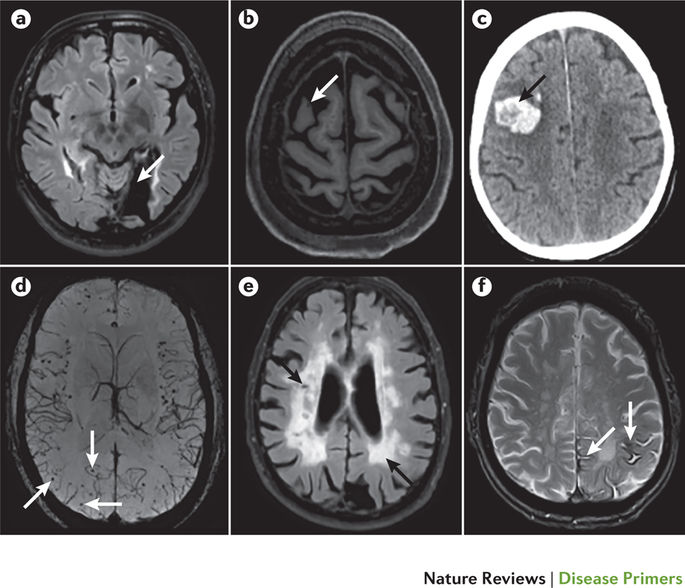

In patients with suspected

#VascularCognitiveImpairment, neuroimaging should be used to assess the extent, location and type of vascular lesions http://go.nature.com/2Etet4C pic.twitter.com/HK5GfKja1y